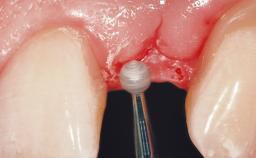

Immediate Placement of an Implant in a Maxillary Left Central Incisor Site

A 33-year-old female patient presented with an upper left central incisor that required extraction after a failed endodontic therapy. The tooth had been traumatized when the patient was a teenager and had undergone several endodontic treatments, including two apicectomy procedures. The patient was in good health and did not smoke. Clinical examination showed that the patient had a high lip line. In full smile, the gingival margins of the upper teeth were visible to the first molars. The gingival margins of central incisors 11 and 21 were only just showing. Examination of tooth 21 confirmed that the tooth was mobile and had hypererupted by 1 mm.

| Soft Tissue Grafting | Simultaneous |

| Placement Protocol | Immediate implant placement |

| Tooth Site | Maxillary incisor or canine |